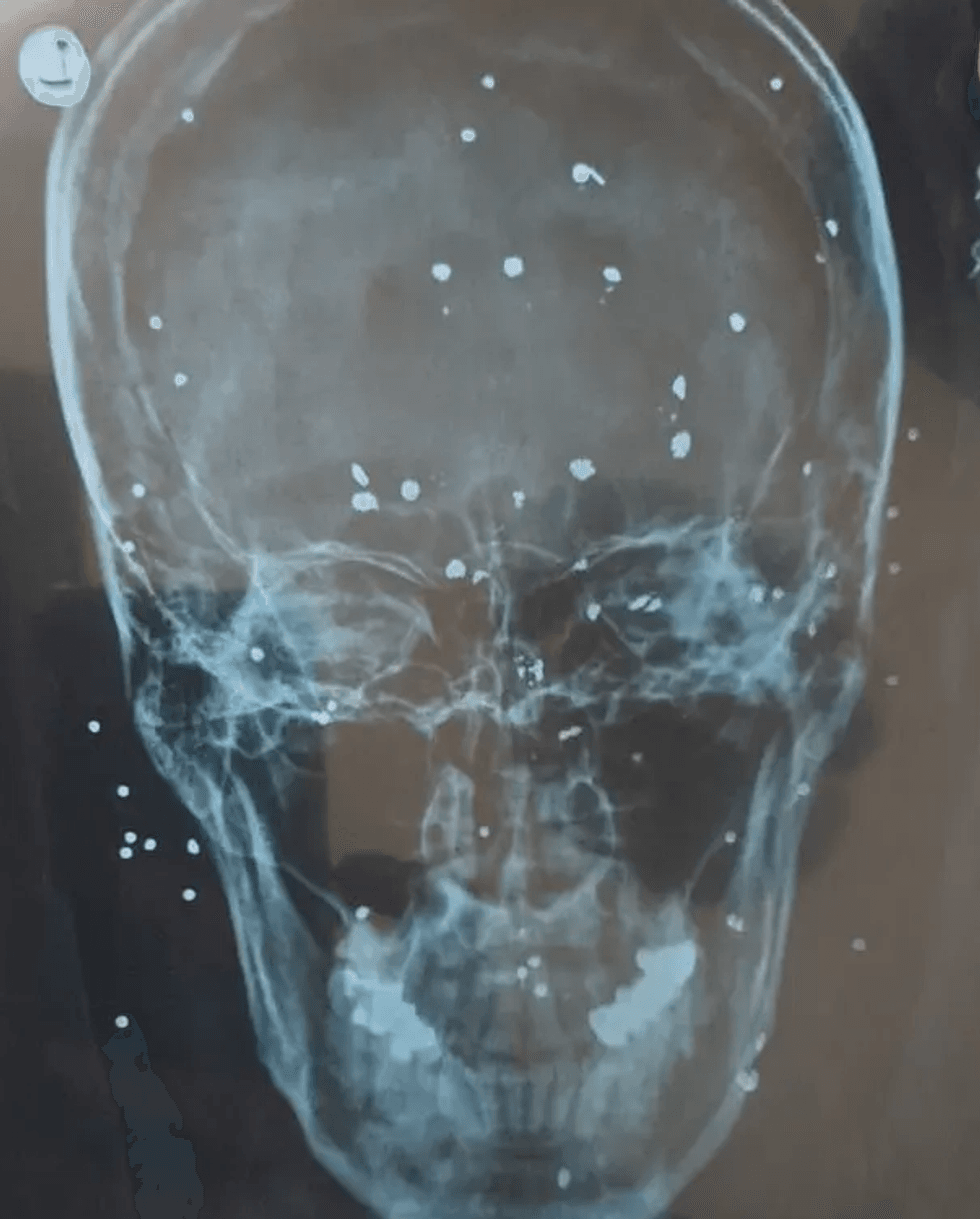

Derisa një ndërprerje e internetit ka fshehur pjesën më të madhe të shtypjes së përgjakshme ndaj protestuesve, fotografitë e ofruara nga mjekët për The Guardian treguan plagë shkatërruese në të gjithë trupin e tyre nga të ashtuquajturat fishekë zogjsh, të cilat forcat e sigurisë i kanë gjuajtur mbi njerëzit nga një distancë e afërt.

Disa nga fotot tregonin njerëz me disa topa të vegjël "të qëlluar" të vendosur thellë në mishin e tyre.

The Guardian ka folur me 10 profesionistë mjekësorë të cilët kanë paralajmëruar për seriozitetin e lëndimeve që mund të lënë qindra të rinj iranianë me dëmtime të përhershme. Të shtënat në sytë e grave, burrave dhe fëmijëve ishin veçanërisht të zakonshme, thanë ata.